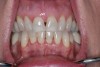

With reduced salivary flow, the mucosa can appear dry and even adhere to examination gloves, gauze, or mouth mirror. The lingual dorsum may exhibit fissures and elongation of the filiform papillae, often described as a coated or hairy tongue (Figure 1). Dental caries may be present, especially in the cervical areas or root caries (Figure 2). Small erythematous macules on the buccal mucosa represent bite marks, which are common with inadequate saliva (Figure 3). Gingivitis (Figure 4), gingival recession, and periodontal disease may be present.14,15

Fig 2. Caries-related tooth loss, dental caries, and abundant dental plaque present in a patient with no salivary flow in 5 minutes.

Figure 2